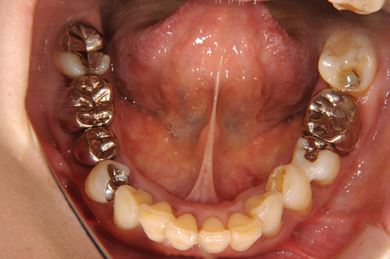

部分矯正治療+骨再生インプラント治療

| 治療方針 | 全体的に骨が薄く、なるべく歯に負担を立てない治療計画にしました。口元も下げたいため、歯を少し細く削り後ろにさげました。部分矯正後、下顎のインプラントも併用しています。 | ||||||||||||||||||||||||||||||||

| 治療内容 | 部分矯正(唇側矯正ホワイト)、インプラント2本(GBR)、メタルボンドセラミッククラウン3本 | ||||||||||||||||||||||||||||||||